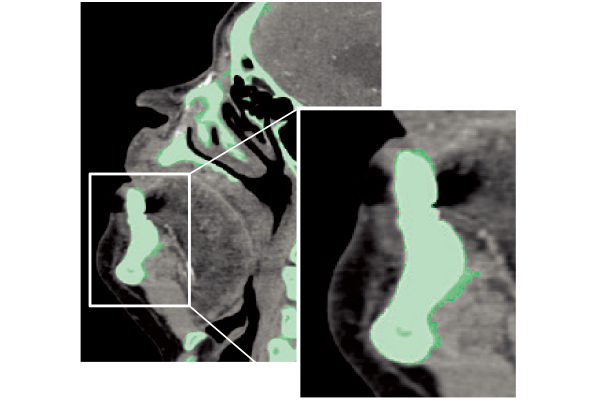

The captured scanogram image can be used to automatically set the scan range. This can be expected to be shorten the setting time. By using Fujifilm's automatic organ segmentation technology*7, which was developed utilizing deep learning, it contributes to the scan of a total of 14 types, including the head and chest. In addition, since the margin of the scan area can be set in advance, the scan area can be customized according to the operation of each facility. The operator can also check and adjust the automatically calculated scan area.

REiLI makes it happen to extract organs and simplify your work.

Kidney